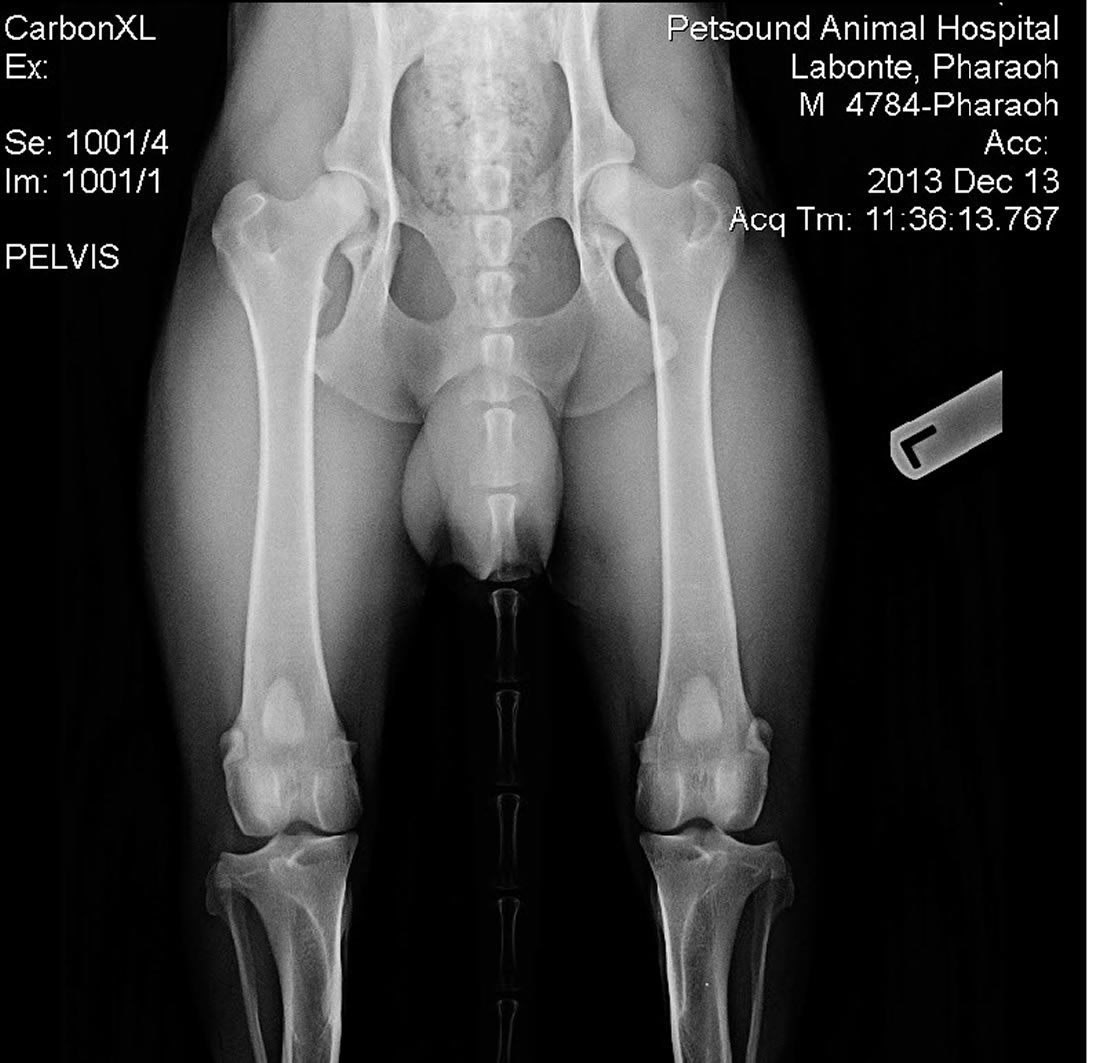

Labonte's Pharaoh - OFA Excellent

Labonte's Pharaoh - OFA Excellent is an extreme prey driven dog and is very fast with a 37mph escape. His hips have the rare OFA rating of Excellent. He is black with a very nice red color and a strong European structure. Pharoah's pedigree is nothing short of awesome. With dogs like Fero, Quinto, Orry and lines like Karthago, Antverpa, Tiekerhook, Korbelbach giving her a very well rounded foundation and strong genes for breeding.